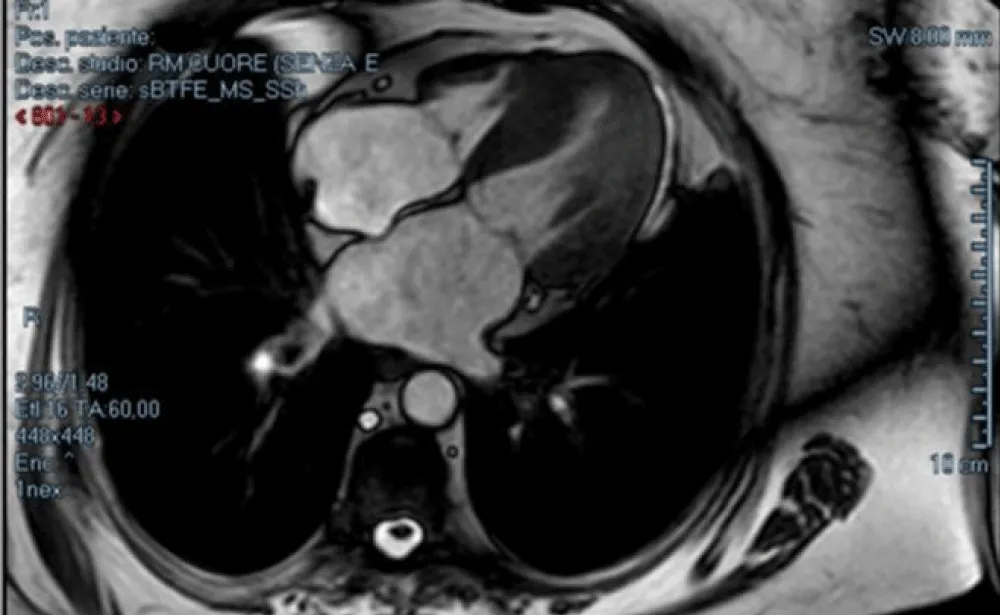

GLS was calculated offline with images obtained from apical windows 4, 3, and 2 chambers. The software automatically calculated the degree of longitudinal deformation. The myocardial was divided into six zones (inferior, infero-septal, antero-septal, anterior, antero-lateral, infero-lateral). The average strain profile of the wall was analyzed for each area. From this analysis, we obtained the systolic peak of longitudinal strain (PSLS: Peak Systolic Longitudinal Strain) which is the maximum negative value of deformation during the ejection phase. The GLS was calculated from the averages of the values obtained by the individual myocardial walls for each window (Figure 1). 2D imaging was used for the calculation of the LVM. The formula for determining the mass was LVM = Area x Height. The area was calculated from the parasternal short-axis window (at the level of the papillary muscles) by subtracting the ventricular cavity from the area calculated at the epicardium level. The height was measured from the 4-chamber window as a base-apex distance. The ventricular mass was also indexed according to the formula LVMi = LVM/BSA. According to the guidelines, the upper reference value was 88 g/m2 in women and 102 g/m2 in men.

Download Image

Figure 1: Bull-eyes of 17 segments, calculating GLS (A) and CW doppler through the aortic valve, which shows severe aortic stenosis (B).